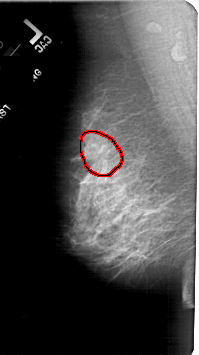

A_1804_1.RIGHT_MLO

RIGHT_CC LINES 5311 PIXELS_PER_LINE 2401 BITS_PER_PIXEL 12 RESOLUTION 43.5 NON_OVERLAY

FILE: A_1804_1.LEFT_CC.OVERLAY

TOTAL_ABNORMALITIES 1

ABNORMALITY 1

LESION_TYPE MASS SHAPE ARCHITECTURAL_DISTORTION MARGINS SPICULATED

ASSESSMENT 4

SUBTLETY 1

PATHOLOGY MALIGNANT

TOTAL_OUTLINES 1

BOUNDARY